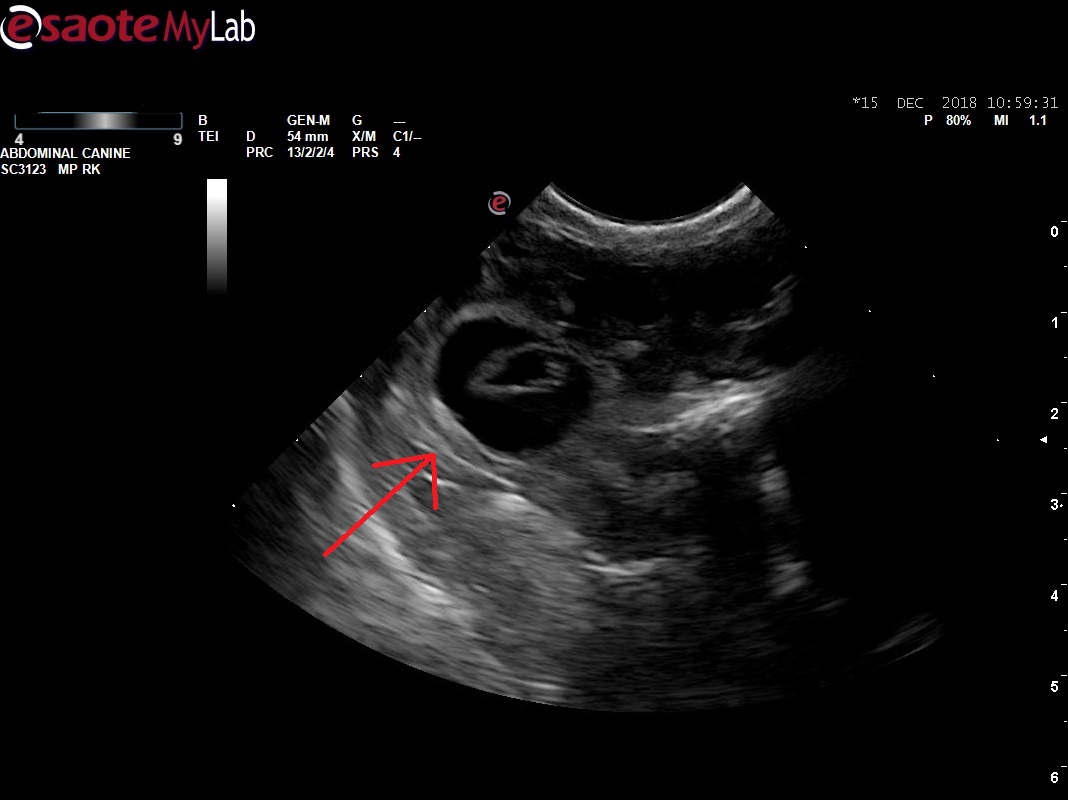

- diagnostika gravidity u suky